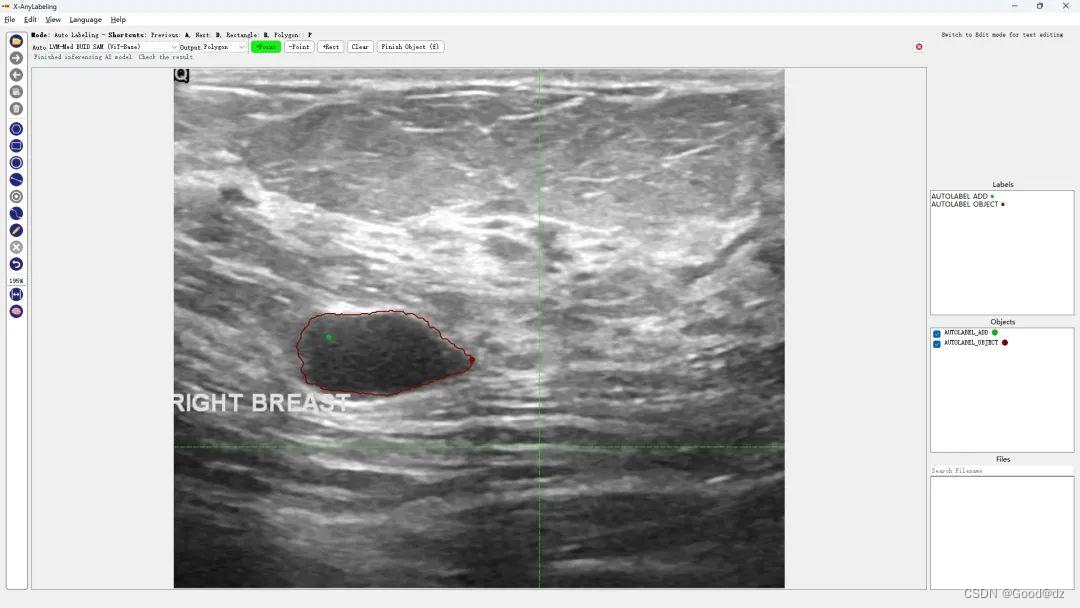

第六:医学图像分割

超声波乳腺癌分割 | 结直肠息肉分割 | 皮肤镜病变分割